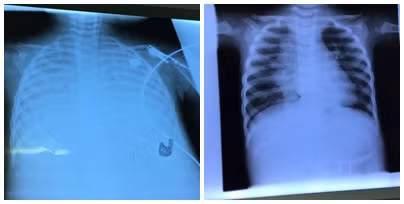

| Phim chụp phổi cháu bé trước (hình trái) và sau khi điều trị bằng kỹ thuật ECMO (hình phải). |